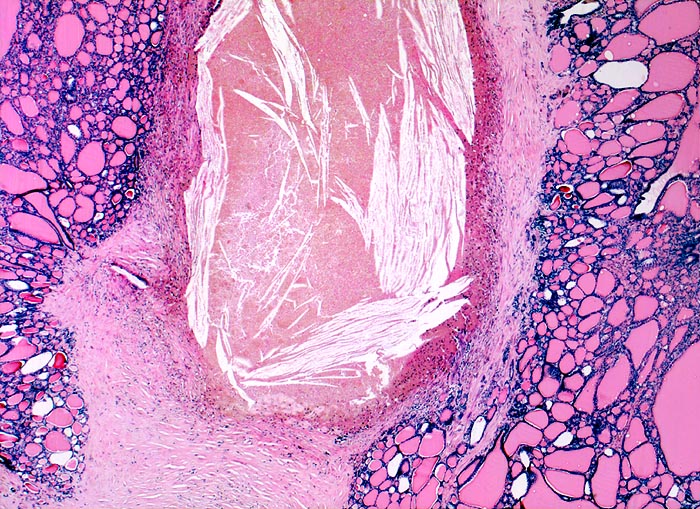

PathoPic ID 3820 - Knotenstruma mit regressiven Veränderungen

Knotenstruma mit regressiven Veränderungen

Hyperplasie / Hypertrophie

Schilddrüse

Endokrinium

Unterschiedlich grosse Follikel. Dazwischen Stromafibrose mit alter Blutung (zahlreiche Cholesterinkristalle).

knotiges Schilddrüsenparenchym.

multinodöse euthyreote Struma mit szintigraphisch kalten Arealen

Histologie

25